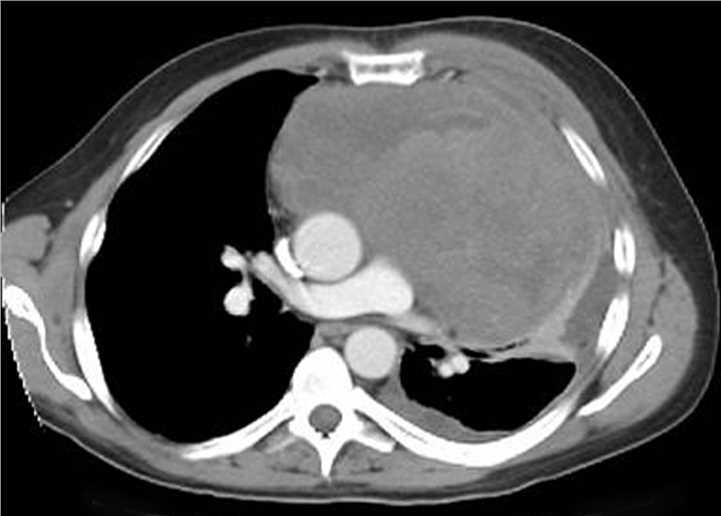

Thrombosis of the superior vena cava caused by an indwelling central venous catheter which caused superior vena cava syndrome.Fig.1 Thrombosis of the superior vena cava caused by an indwelling central venous catheter. Distributed under CC BY-SA 3.0, from Wiki, without modification.